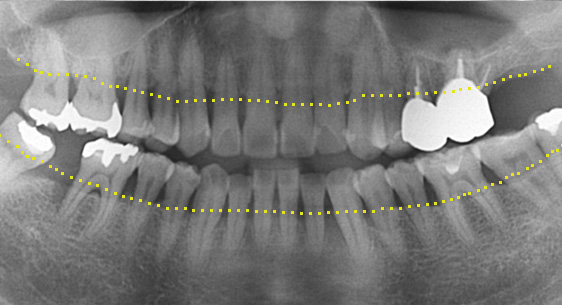

신경관이 막혀 있는 경우 재 신경치료로 낫지 않는 경우, 포스트가 있어 재 신경 치료를 할 수 없는 경우, 치아 뿌리까지 염증이 심하지만 이러한 염증을

제거 할 수 없는 경우, 고운미소 치과에서는 치조골 주위 염증조직을 제거하는 치근단절제술을 시행합니다.

기존 신경치료는 양호한 상태이나 치근부위에 염증과 치조골 소실이 진행 중

치아 뿌리 쪽 잇몸을 절개하고 치조골 부위의 염증조직을 제거. (난이도 중)